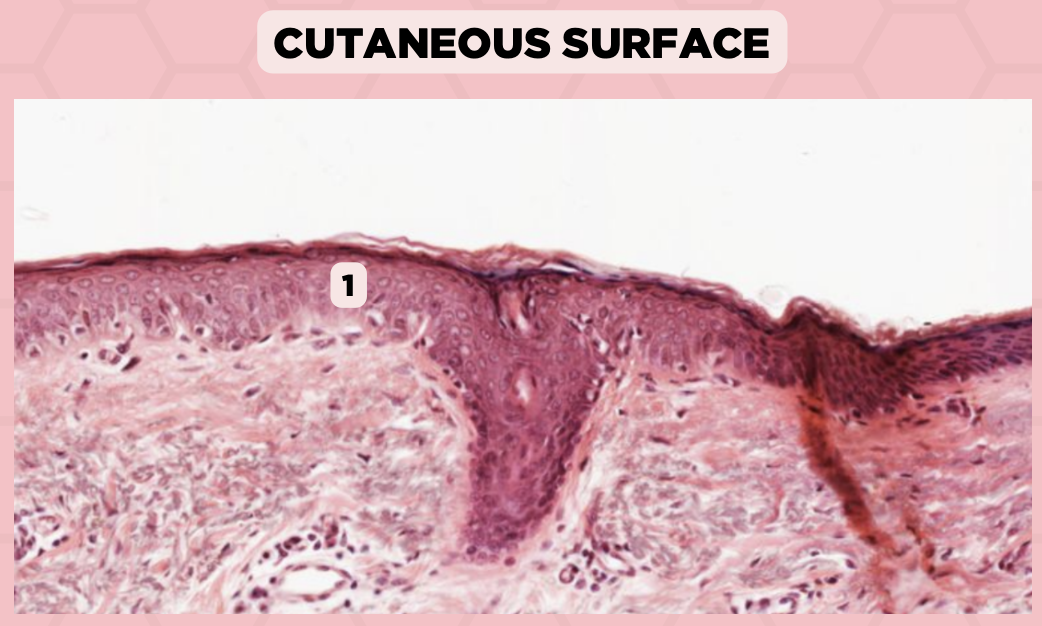

a. Abrupt Transition from keratinized to nonkeratinized epithelium

Identify the structure’s lining epithelium given in the image?

a. Abrupt Transition from keratinized to nonkeratinized epithelium

b. Abrupt Transition from nonkeratinized to keratinized epithelium

c. AOTA

d. NOTA

Lip

What specimen is being showed in the picture?

Mucocutaneous Junction

Identify the structure labeled as 1.